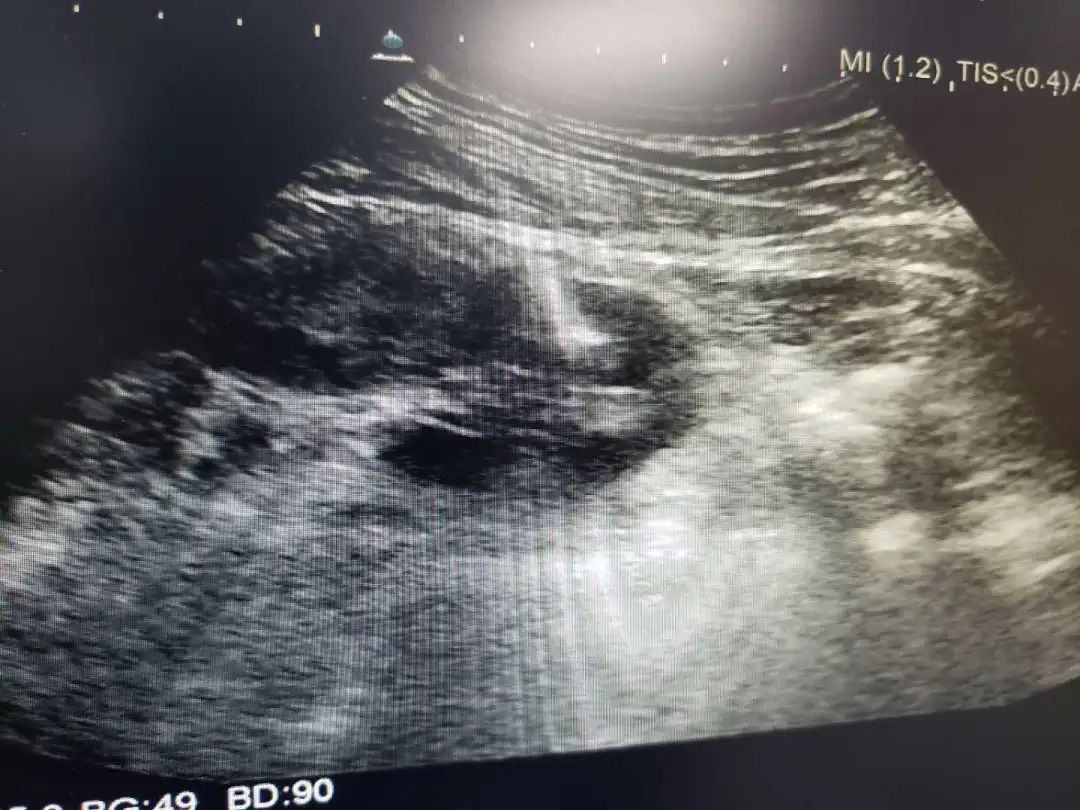

超声引导下肿瘤消融治疗是在实时超声的监视引导下应用专门的治疗针,达到不开刀、对体内的肿瘤原位灭活的一门新技术,其中肝癌经皮微波凝固治疗处国际领先地位。

微波消融治疗肝癌可采用经皮穿刺、开腹手术术中消融或经腹腔镜引导几种方式,超声引导下准确地摆放微波辐射电极,保证凝固坏死区完全覆盖整个肿瘤,达到完全灭活肿瘤。对于小于3厘米的肝癌,射频、微波消融治疗技术成熟,已经取得和手术相同的临床效果,但微创、安全、经济、痛苦小是手术方法无法替代的,尤其是无法耐受手术及复发和转移的肝癌。